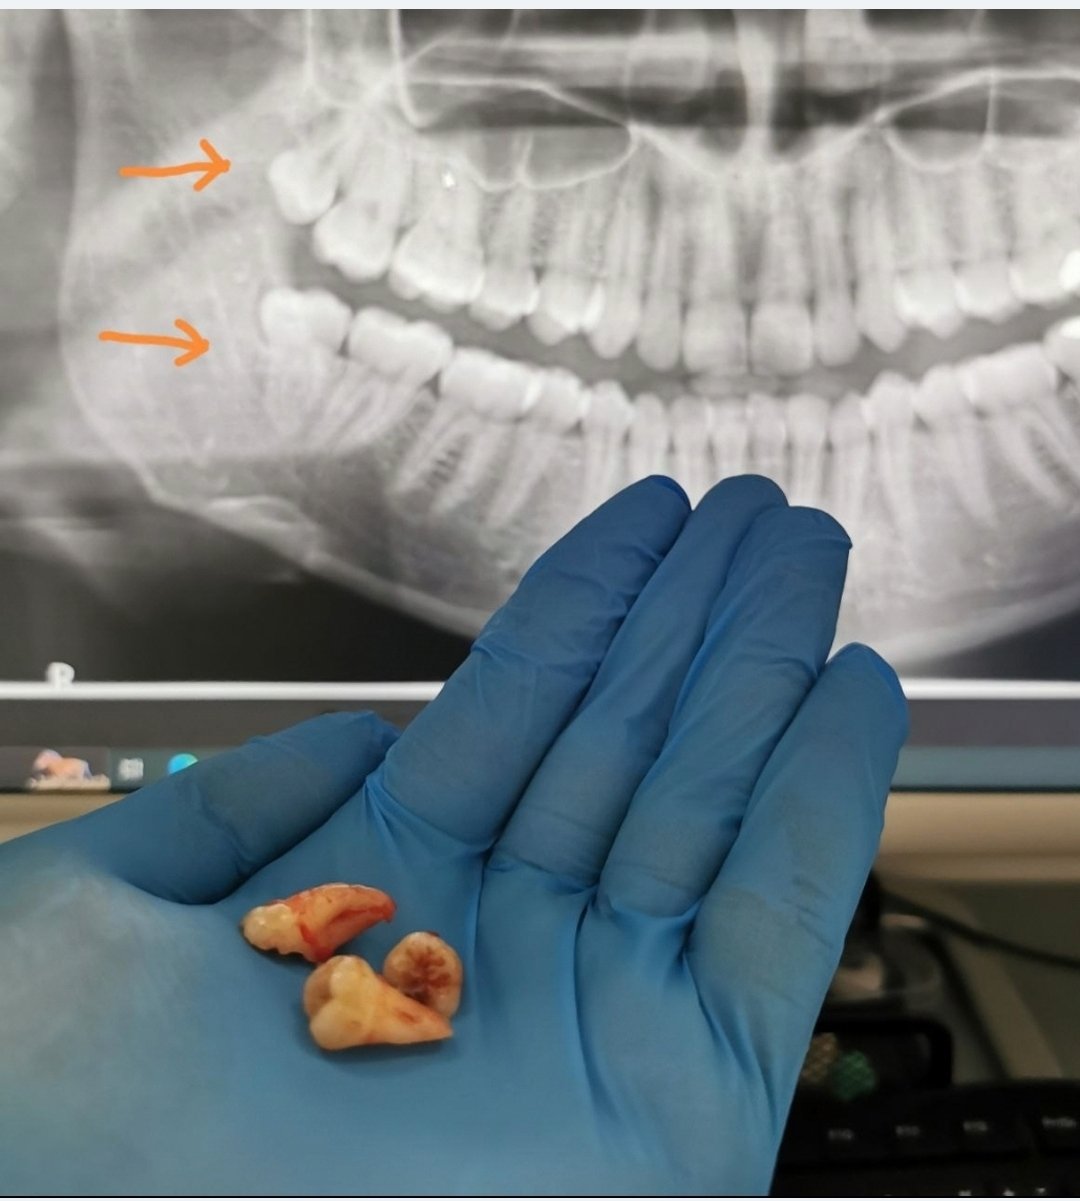

Zubná chirurgia – stomatochirurgia

Extrakcia/vytrhovanie zubov a stomatochirurgické zákroky.

Fotografie